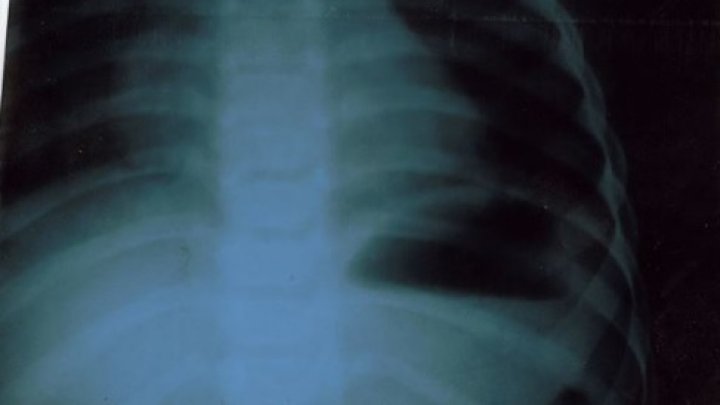

O copilă de 2 ani şi 6 luni a ajuns la spital după ce a înghiţit o monedă de un leu. Fetiţa a fost transportata la Institutul Mamei şi Copilului, unde medicii din candrul secţiei Endoscopie.

Victor Rașcov (medic endoscopist), Semeniuc Alexandra (asistentă medicală), Glijinschi Anastasia (anesteziolog), au conlucrat în procedura de extragere cu succes a monedei din tractul digestiv al fetiţei.

Situaţia nu este fără precedent. Potrivit datelor centrului medical, de la începutul acestui an a fost efectuate deja 16 intervenții de extragere a corpurilor străine din tractul digestiv superior la copii, dintre care în 7 cazuri fiind vorba de înghițirea unor monede.